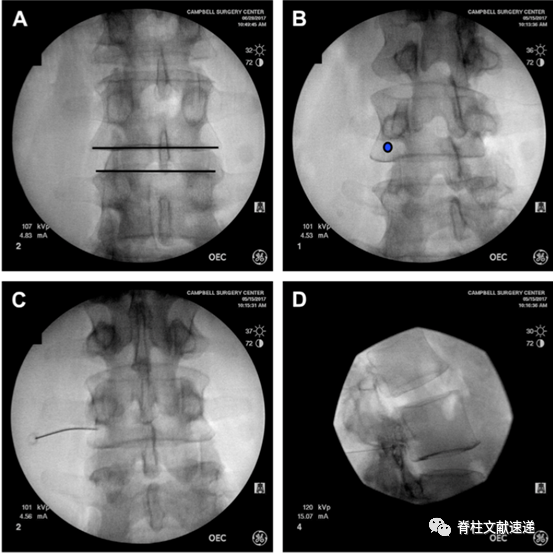

1.1俯卧位,常规消毒,定位,正位时调整C臂机,使目标椎间隙平行(上图A)

1.2.穿刺的靶点是椎体后缘、椎弓根外下缘、出口根上方,见蓝点(上图B)。

1.3.透视正位,针尖位于椎弓根的外下缘(上图C),透视侧位,针尖紧贴椎弓根下方(上图D)。

1.4.穿刺位置良好后,抽吸测试,若无血液和脑脊液,可行造影剂观察(上图E),再行局麻药物注入,观察症状缓解情况。